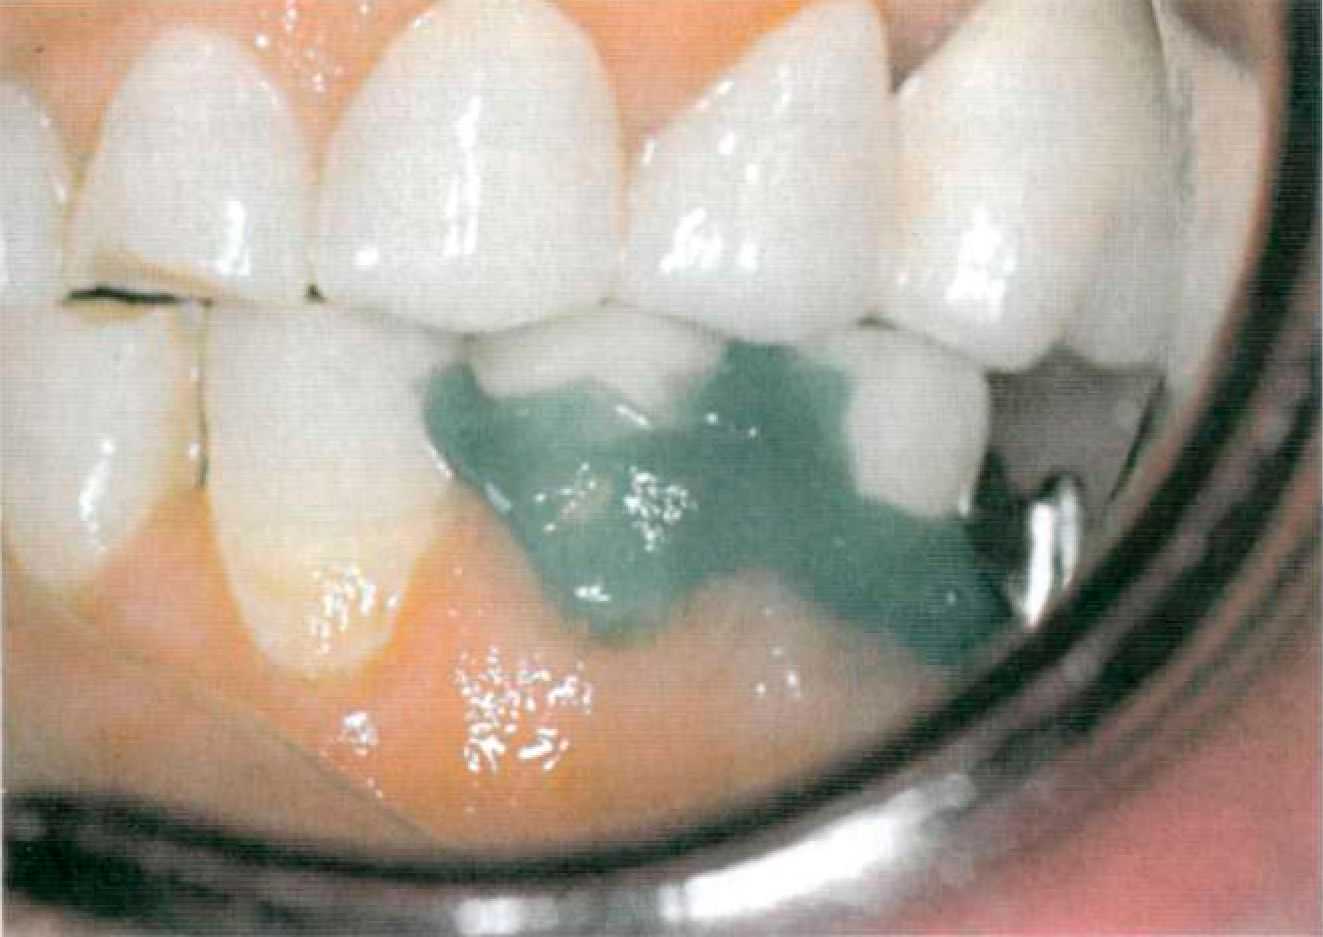

Этап 5. После нанесения зубным техником керамической облицовки в клинике проводят припасовку металлокерамических коронок опорных зубов (рис. 109). Выверяют окклюзионные контакты, цвет. Этап 6. После глазуровочного обжига коронки фиксируют в полости рта на корригирующий оттискной материал для избежания смещения (рис. 110) и снимают оттиск для изготовления съемной части комбинированного протеза. Возможно применение индивидуальной ложки, изготовленной по предварительному альгинатному оттиску. Опорные коронки с замковыми креплениями переходят в оттиск (рис. 111). Этап 7. В лаборатории опорные коронки заливают воском и по полученному оттиску изготавливают рабочую модель (рис. 112). К замковому креплению, установленному на опорных коронках, присоединяют комплементарную часть (рис.113) или ее аналог. В зависимости от типа замкового крепления и конструкции съемной части протеза модель дублируют или проводят моделировку каркаса на рабочей модели, используя беззольную пластмассу (рис. 114).

После литья изготовленный каркас припасовывают на модели (рис. 115). Затем проводят окончательную отделку каркаса, постановку зубов на воске, замену воска на пластмассу, окончательную отделку протеза. Для многих конструкций замковых креплений именно на этом этапе фиксируют вторую часть аттачмена в каркасе съемной части протеза.

Этап 8. На заключительном этапе проводится проверка готового протеза в полости рта (рис. 116). Оценивают точность посадки аттачмена, проводят коррекцию окклюзионных контактов. Проверяют функции аттачмена (изначально он не должен быть активирован). Цементирование несъемной конструкции осуществляют под контролем надетой съемной части. Между патрицей и матрицей должен быть помещен вазелин для предотвращения попадания цемента.